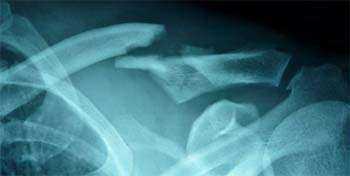

Une radiographie suffit en général à confirmer le diagnostic d’une fracture de la clavicule et à déterminer son degré de gravité. Elle permet de préciser le site de la fracture sur la clavicule, de déterminer le déplacement, le nombre, la taille et la position des différents fragments.

Dans certains cas, un scanner avec reconstruction en 3 dimensions peut être utile pour mieux évaluer la position des fragments. Une échographie avec doppler peut être utilisée en cas de suspicion d’une lésion vasculaire associée à la fracture. Un électromyogramme (EMG) est également demandé si on suspecte une atteinte des nerfs adjacents (plexus brachial).